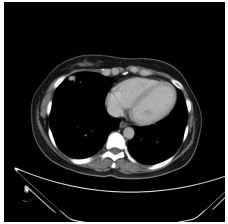

7. 27 y/o male, progressive DOE for weeks